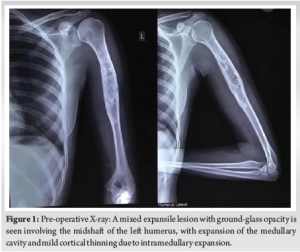

A 22-year-old female patient presented with complaints of pain in her left arm on and off for the past 2 years, which had been aggravated over the last 1 month. Pain is an insidious, progressive, non-radiating, dull aching type, aggravated on physical activity, relieved on rest. Patient had an alleged history of trauma 6 years back (skid and fall at her residence) sustaining injury to left arm and diagnosed to have a humerus fracture and lytic lesion. For which she was treated conservatively at an outside hospital. After 2 months of the fracture, the patient sustained again fracture over the same site and opted for conservative treatment. After 2 months of refracture aspiration (~50 mL) under CARM Guidance at SBMCH was done. On examination, no scar, sinus, or obvious swelling was noted. No soft tissue/bony tenderness seen. Range of motion (shoulder and elbow) was full and free without distal neurovascular deficit (DNVD). Blood investigations were carried out and found to be normal. X-ray (Fig. 1) showed mixed ill-defined lytic expansile lesions with a narrow zone of transition over the proximal 2/3rd of the left humerus. After the surgical procedure, the curettage bone was sent for histopathology (Fig. 2) and reported as fungal infection.

This case was reported due to its rarity and diagnostic complexity. While fibrous dysplasia is a known benign lesion with distinct radiological features, this case demonstrates that fungal infections can closely mimic such lesions both clinically and radiographically. The unexpected histopathological finding of fungal spores in an immunocompetent patient underscores the importance of maintaining a broad differential diagnosis when evaluating bone lesions. The incidence of fungal infection of bones and joints is usually low and rare. Invasive fungal infections are more likely to be associated with a rising population of immunosuppressed patients [7], and are also seen in patients with several comorbid conditions. Patients under steroid treatment are likely to be immunosuppressed and are prone to acquiring infections. Species such as Candida and Aspergillus are the most common causative organisms [8]. Candida, being an endemic dimorphic fungus, is accountable for an enormous number of cases globally. Fungal infections are commonly transmitted through the hematogenous route. Transmission from contiguous infection, or by direct inoculation following trauma or surgery, is also noted. Clinically, adults present with mild features, often without fever or a rise in inflammatory markers. Children may have features of vertebral osteomyelitis, which differ from adult presentations [9]. Due to the dormant nature of symptoms in adults, diagnosis is often delayed. Diagnosis is based on tissue culture, tissue histology, and clinical correlations. In this case, the X-ray findings (Fig. 1, 2) mimicked fibrous dysplasia, showing a mixed expansile lesion with ground-glass opacity. The patient was clinically and radiologically (Fig. 3-5) diagnosed to have fibrous dysplasia. However, histological examination revealed a fungal infection. Therefore, to avoid misdiagnosis, tissue culture and histology are necessary in similar presentations. Once diagnosed, appropriate antifungal medication and often surgical debridement are required.